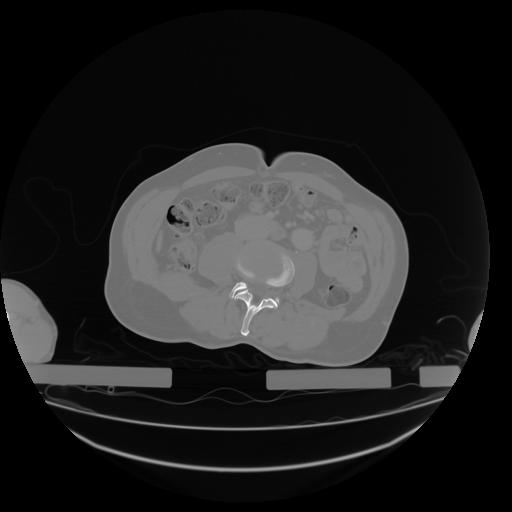

27 CUERPO,CE,Axial,3.0,CUERPO,,